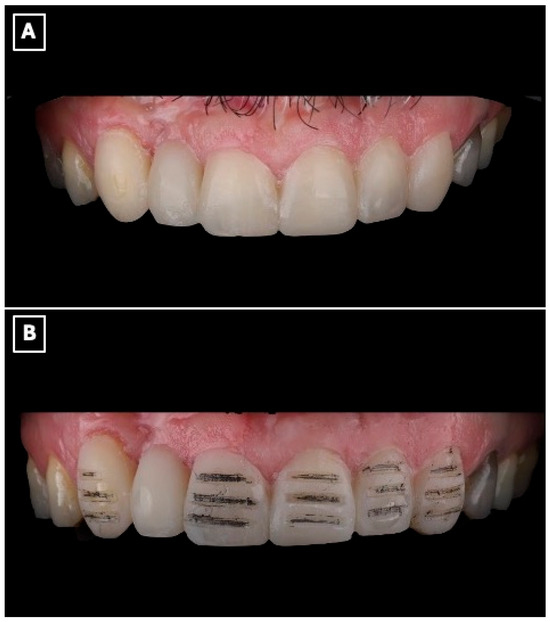

A silicone putty index (Express™ STD Putty, 3M ESPE, St. Paul, MN, USA) was fabricated from the printed diagnostic wax-up, and an intraoral mock-up was performed using a bis-acryl provisional material (Protemp™ 4, 3M ESPE, St. Paul, MN, USA) (Figure 3A). The mock-up enabled clinical evaluation of tooth proportions, incisal edge position, and smile integration, and served as a communication tool to confirm esthetic acceptance with the patient before performing any irreversible procedures.

Figure 3.

Digital wax-up used for esthetic analysis and prosthetic planning of the anterior rehabilitation. (A) Virtual representation of the maxillary anterior region before wax-up, serving as a baseline for evaluating tooth position, incisal edge discrepancies, and space availability for the planned resin-bonded fixed dental prosthesis. (B) Digital wax-up design illustrating the proposed single-retainer cantilever resin-bonded fixed dental prosthesis and laminate veneers, with idealized tooth proportions, incisal edge position, and symmetry used to guide enamel-confined tooth preparation, pontic emergence profile, and overall esthetic integration within the smile.

Tooth preparation was performed under mock-up guidance to ensure minimal enamel reduction and to create optimal enamel-bonding surfaces (Figure 3B). Final impressions were obtained using a polyvinyl siloxane impression material (Imprint™ 4 PVS, 3M ESPE, St. Paul, MN, USA) and submitted to the dental laboratory for definitive fabrication.

Beyond its role in visualization, the digital wax-up and intraoral mock-up contributed directly to clinical decision-making and execution. The digitally planned wax-up enabled precise control of tooth proportions, incisal edge position, and pontic emergence profile, facilitating enamel-confined preparation and preservation of sound tooth structure. The intraoral mock-up functioned as a reduction guide during tooth preparation, minimizing unnecessary enamel removal and reducing chairside adjustments at the time of prosthesis seating. This digital-to-clinical transfer enhanced treatment predictability by allowing preoperative verification of esthetics and function, thereby improving clinical efficiency and patient acceptance.